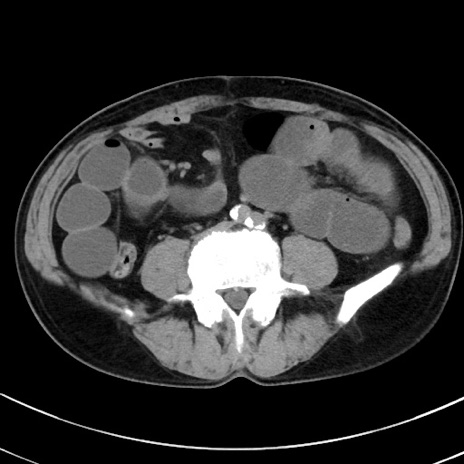

症例38(横断像)

冠状断像

【症例】70歳代 男性

【主訴】腹痛・嘔吐

【現病歴】昨晩より、嘔吐・腹痛あり。今朝になっても嘔吐あり。来院。

【既往歴】心臓バイパス手術、開腹胆摘、腸閉塞

【身体所見】BP 107/71mmHg、HR 116/min、腹部:平坦、軟、下腹部に軽度圧痛あり。反跳痛なし。

【データ】WBC 15100、CRP 0.32